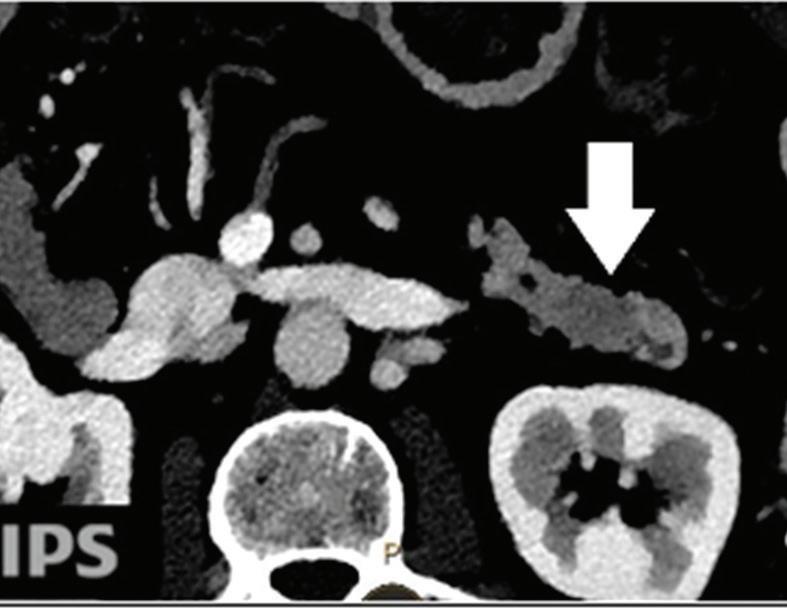

Effectiveness of spectral CT imaging for detection of a peritoneal implant from a renal cell carcinoma invading the bowel wall (arrow). (a) Coronal contrast-enhanced conventional CT image obtained in the arterial phase, corresponding (b) Z effective, (c) monoenergetic 50 keV, and (d) iodine-density image.